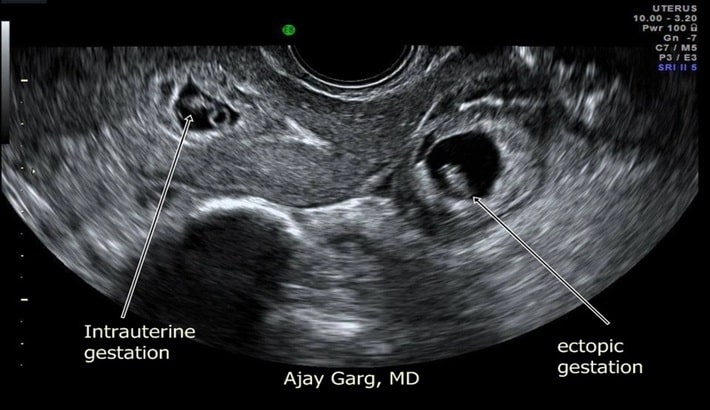

نقش سونوگرافی در تشخیص بارداری خارج رحمی

یکی از روشهای اصلی در تشخیص مشکلات بارداری، سونوگرافی است. بارداری خارج رحمی زمانی رخ میدهد که جنین به جای رحم، در لولههای فالوپ یا سایر بخشهای بدن مادر لانهگزینی کند. این وضعیت میتواند بسیار خطرناک باشد و در صورت عدم تشخیص به موقع، جان مادر را تهدید کند. سونوگرافی، بهخصوص سونوگرافی واژینال، از مهمترین ابزارهای تشخیصی در این شرایط به شمار میآید.

تشخیص زودهنگام بارداری خارج رحمی با سونوگرافی

تشخیص سریع و دقیق بارداری خارج رحمی از بروز عوارض جدی مانند پارگی لوله فالوپ و خونریزی داخلی جلوگیری میکند. پزشکان معمولاً ابتدا با آزمایش خون سطح هورمون hCG را بررسی میکنند؛ سپس به کمک سونوگرافی وجود یا عدم وجود ساک حاملگی داخل رحم را مشخص میکنند.

مزایای سونوگرافی در بررسی بارداری خارج رحمی

سونوگرافی به پزشک امکان مشاهده دقیق لولههای فالوپ، رحم و لگن را میدهد. با این روش میتوان وجود توده مشکوک در لوله فالوپ یا مایع آزاد در لگن را تشخیص داد که از نشانههای خونریزی داخلی است. به دلیل دقت بالا، سونوگرافی واژینال معمولاً به عنوان اولین انتخاب در بررسی بارداری خارج رحمی مورد استفاده قرار میگیرد.

چه زمانی سونوگرافی برای بارداری خارج رحمی لازم است؟

اگر خانمی با علائمی مثل درد شکمی شدید، خونریزی غیرطبیعی، سرگیجه یا ضعف شدید مراجعه کند؛ پزشک معمولاً انجام سونوگرافی را ضروری میداند. این روش کمک میکند تا پزشک تصمیم بگیرد که بیمار نیاز به دارو، جراحی یا صرفاً تحت نظر بودن دارد.